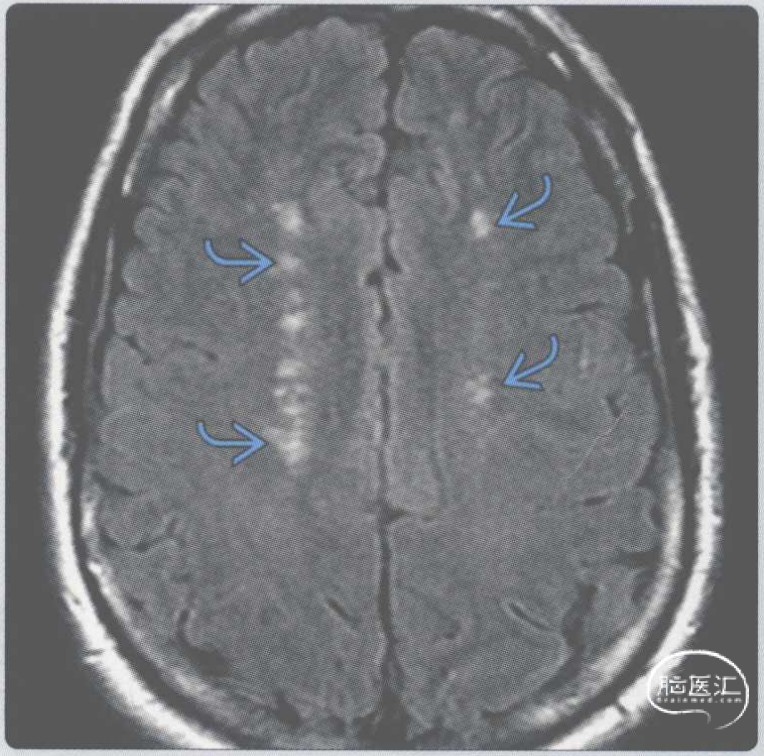

【影像时间·183】一位有蜱咬伤史和游走性红斑的患者